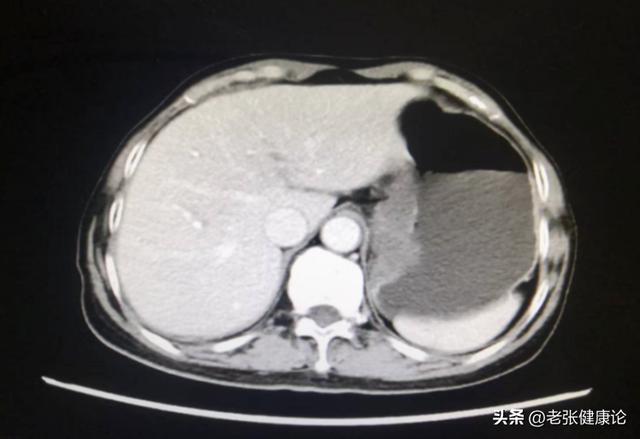

幽门螺杆菌:与约70%的胃癌相关,可通过口耳相承、共餐、共用餐具等形式在家庭中传播。乙肝病毒(HBV):与原发性肝癌关系密切,国内不少肝癌患者齐有乙肝病毒感染史。